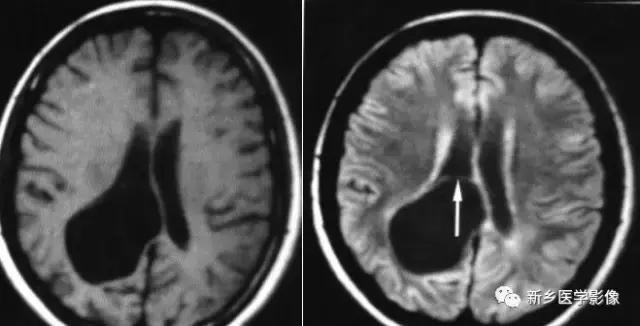

8.胼胝体发育不良

在脑发育腹侧诱导晚期,新形成的端脑嘴侧壁的背侧部分增厚、内陷,向后沿尚未完全发育的大脑半球间裂延伸。两个月后形成一个连合即胼胝体纤维的细胞框架,该细胞框架形成后胼胝体相应部分立即发育。膝部先发育。然后是体部、压部.位于胼胝体膝部后下方的胼胝体嘴最后发育。如果胼胝体发育过程中出现有害因素,就有可能导致胼胝体发育不良.表现为完全缺如或部分缺失。常表现为膝部存在或膝部和体部存在。压部和胼胝体嘴缺失。

胼胝体发育不良可见单独发病,但更常见的是伴有中枢伸经系统的其他畸形,包括胼胝体周围脂肪瘤、脑膨出、交通性脑积水Chaiarii畸形、Dandy-Walker囊肿、脑裂畸形等。临床上可无症状或仅有轻度临床症状,临床检查可见眼距过宽、大头畸形、智力发育迟滞等。胼胝体缺失时,MR冠状位上侧脑室前角呈新月形表现,侧脑室体部分离,呈垂直状平行走行。